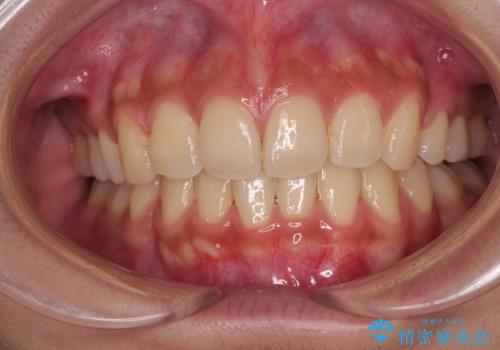

正面や横からの写真ではきれいに治っており、患者様は大変満足のいく仕上がりとなりましたが、深い咬み合わせの改善は不十分で、奥歯の咬み合わせも改善させることができませんでした。

インビザラインは、咬合力の強い方ですと、奥歯が歯肉内にめり込んでしまうため、前歯が強く接触してしまうことがあります。

こちらの方は、奥歯はしっかりと噛んだのですが、歯肉にめり込んでしまったことで、歯肉が腫れやすくなってしまいました。